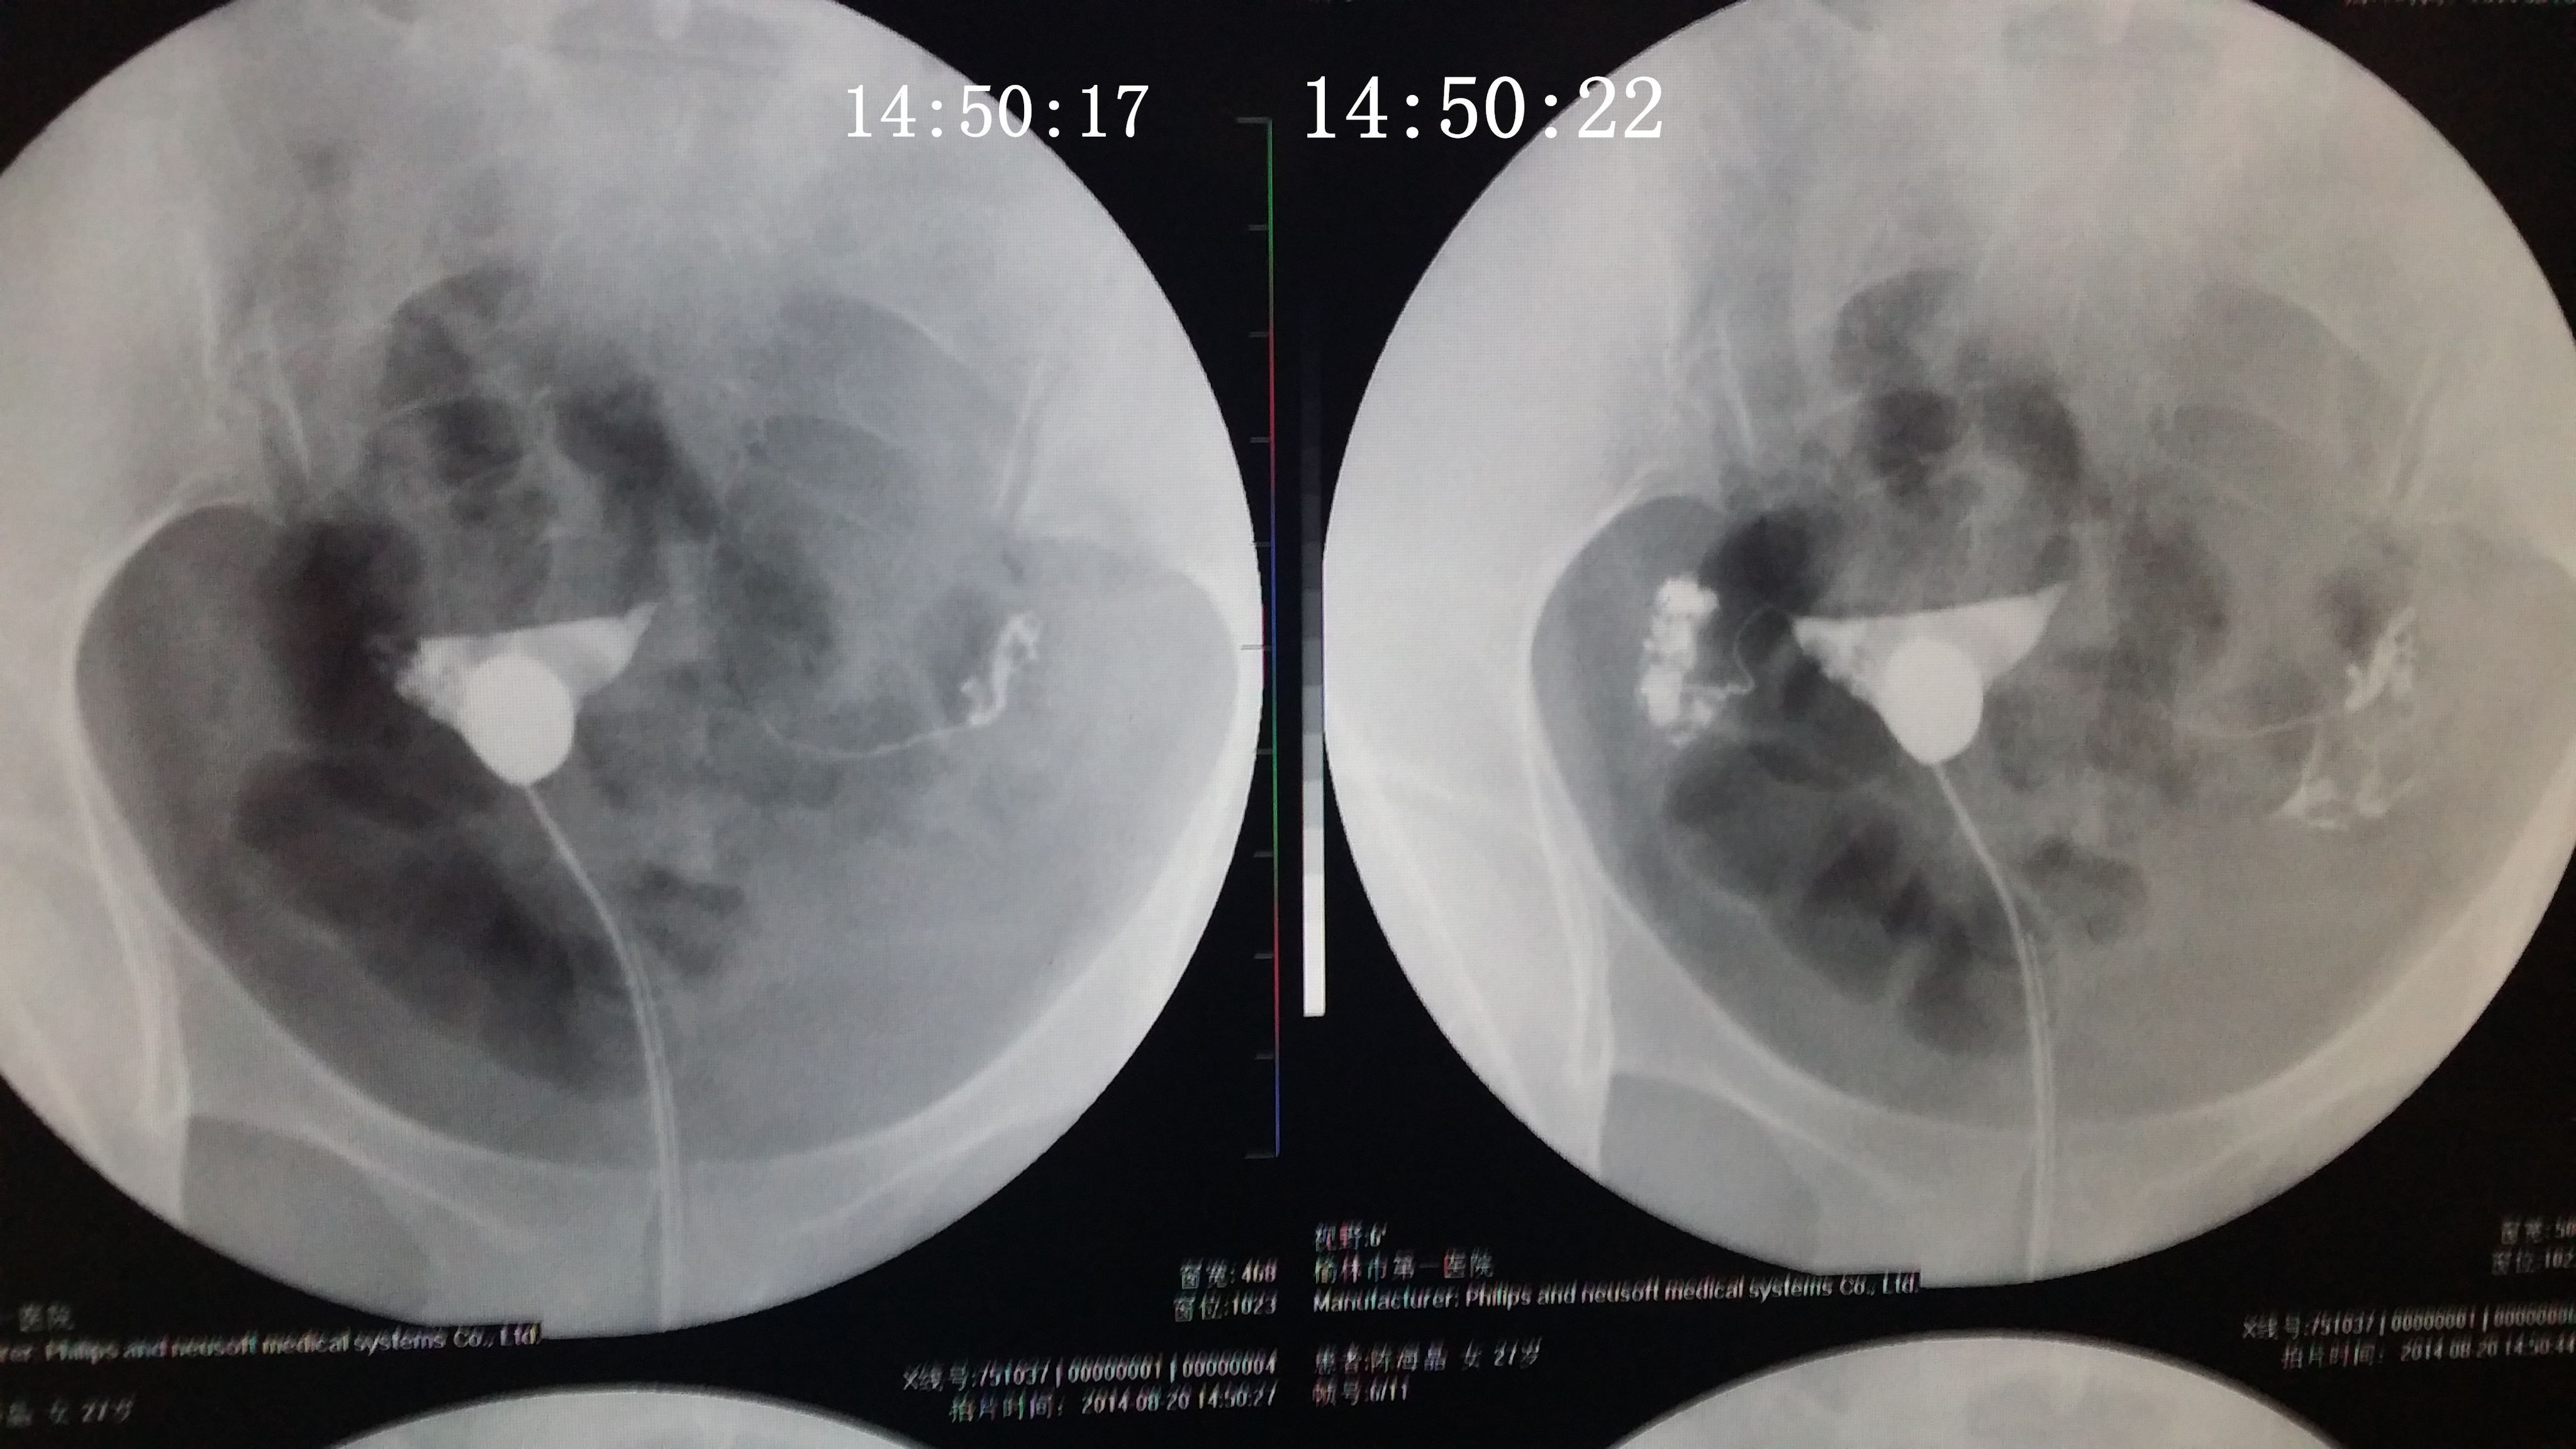

请专家帮我分析下我的造影片 医生诊断说是没问题,只是右侧输卵管伞部有点弯曲不直,说左侧通着可 以自然受孕,不知道会不会有错,之前在其他医院没做造影直接做的通液,说是阻力很大,堵的厉害后过几个月在另一家医院做的这个造影片。(另之前有过盆腔积液,但已经治疗好了} 造影都好几天了右侧一直觉得酸痛的,是不是又发炎了啊,吃药可以吗? 点击展开 匿名用户 2014-09-04 20:09 为您推荐: 其他回答 你好,这个还好的啊,这个不是已经通过了里面,这个这样就是不会有什么事情的 的哦 生活还在继续66 2014-09-05 14:56 相关问题 输卵管通而不畅,迂曲右侧上举,请问济南哪个大医院治疗这个专业啊~请有经验的人告诉下~急急急另附造影片 输卵管伞端不通怎么办 如果排了,B超能检测出来吗?B超单上会显示什么?12月22号做的造影,结果是右侧输卵管伞端通而不

以自然受孕,不知道会不会有错,之前在其他医院没做造影直接做的通液,说是阻力很大,堵的厉害后过几个月在另一家医院做的这个造影片。(另之前有过盆腔积液,但已经治疗好了} 造影都好几天了右侧一直觉得酸痛的,是不是又发炎了啊,吃药可以吗?